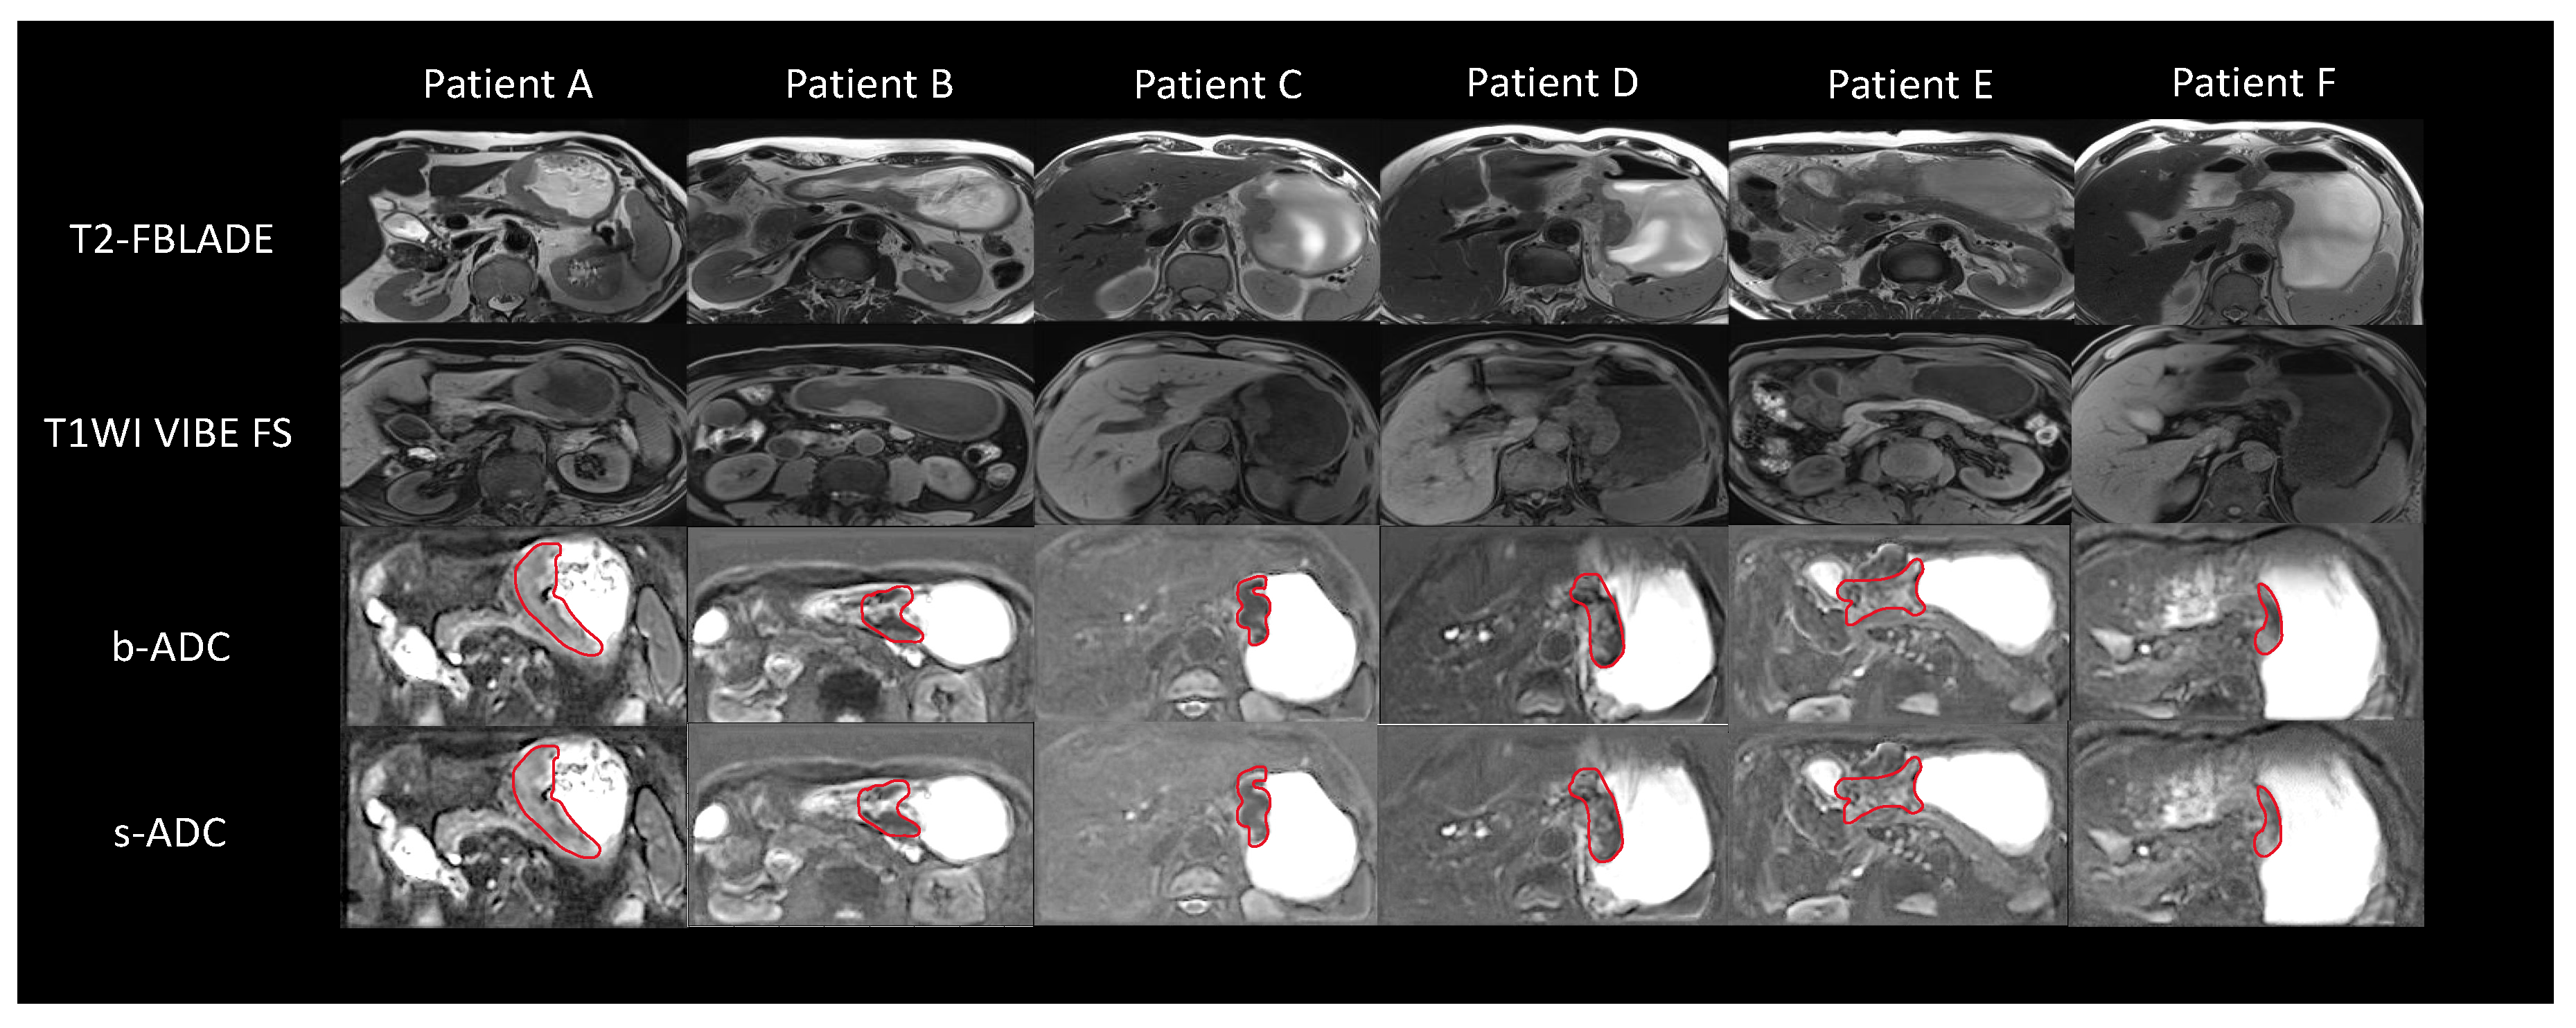

3.4. ADC Measurement Assessment Results and Analyses

| ADC Dataset | Liver | Kidney | Gastric Cancer Lesion |

|---|---|---|---|

| b-ADC | 0.89 (0.84–0.94) | 0.90 (0.83–0.96) | 0.87 (0.79–0.93) |

| s-ADC | 0.89 (0.85–0.96) | 0.89 (0.81–0.94) | 0.88 (0.81–0.97) |

| Reader | ROI | b-ADC | s-ADC |

| Reader1 | Liver | 0.86 (0.80–0.89) | 0.85 (0.83–0.89) |

| Reader2 | Liver | 0.87 (0.82–0.90) | 0.89 (0.80–0.92) |

| Reader1 | Kidney | 0.85 (0.80–0.89) | 0.86 (0.80–0.89) |

| Reader2 | Kidney | 0.86 (0.82–0.89) | 0.90 (0.80–0.93) |

| Reader1 | Gastric Cancer Lesion | 0.86 (0.84–0.88) | 0.93 (0.84–0.97) |

| Reader2 | Gastric Cancer Lesion | 0.87 (0.83–0.92) | 0.92 (0.88–0.96) |